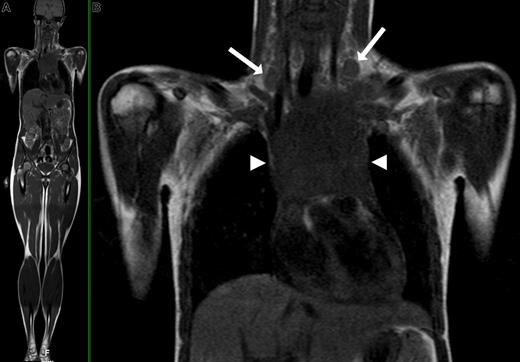

Although MRI inherently provides superior soft-tissue contrast to CT and has the potential to characterize lesions on the basis of signal characteristics, assessment of nodal involvement is still based on size criteria, where lymph nodes with a short-axis diameter greater than 10 mm are generally considered positive (similar to CT). General criteria for extranodal involvement are any signal abnormalities or mass lesions involving soft tissues, bones, parenchymal organs, and serosal cavities (Figure 2).

WB-MRI of a 16-year-old female with Hodgkin disease. (A) Coronal T1-weighted WB-MRI. (B) Close-up image shows bilateral enlarged cervical lymph nodes (arrows) and a large mediastinal mass (arrowheads) consistent with confluent lymphadenopathy.